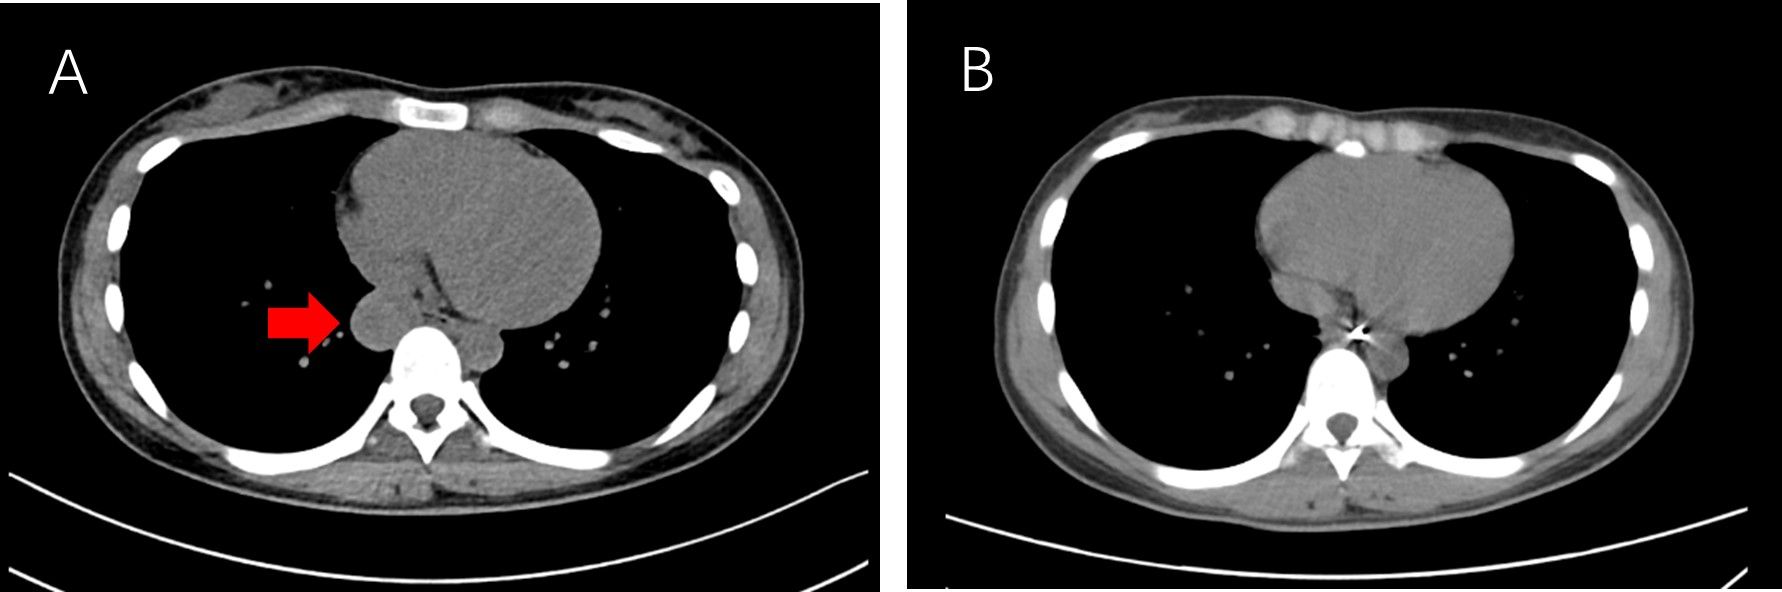

A.术前胸部CT见后纵膈食管旁肿物(红色箭头) B.术后复查未见肿物

今年25岁的余女士,体检时发现后纵膈存在直径约3厘米的肿物,紧邻食管及纵膈大血管。若肿物持续增大,可能压迫周围器官导致呼吸困难或吞咽困难。

最终,团队仅用时不足1小时即成功完整切除肿物,并以金属夹封闭食管隧道入口,术后未出现并发症。术后病理结果显示,肿物为良性支气管源性囊肿。